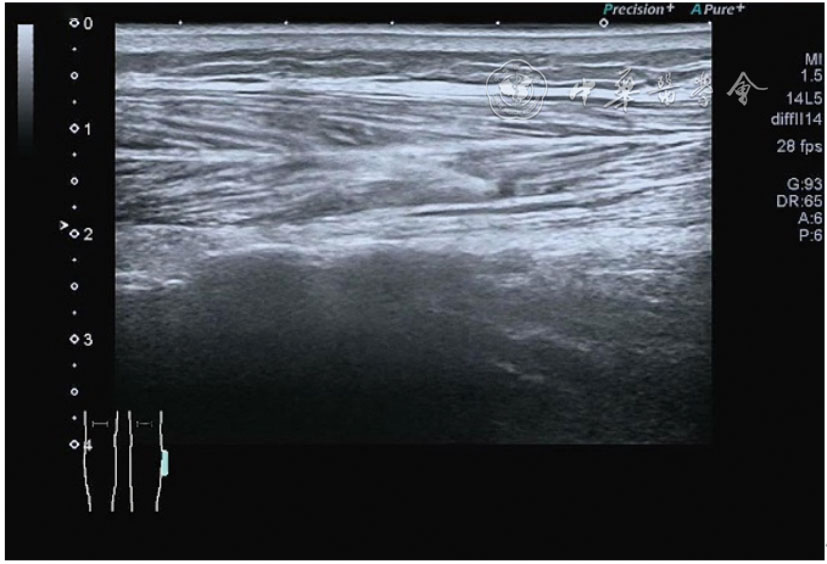

Ultrasonic diagnosis and treatment of knee musculoskeletal pain